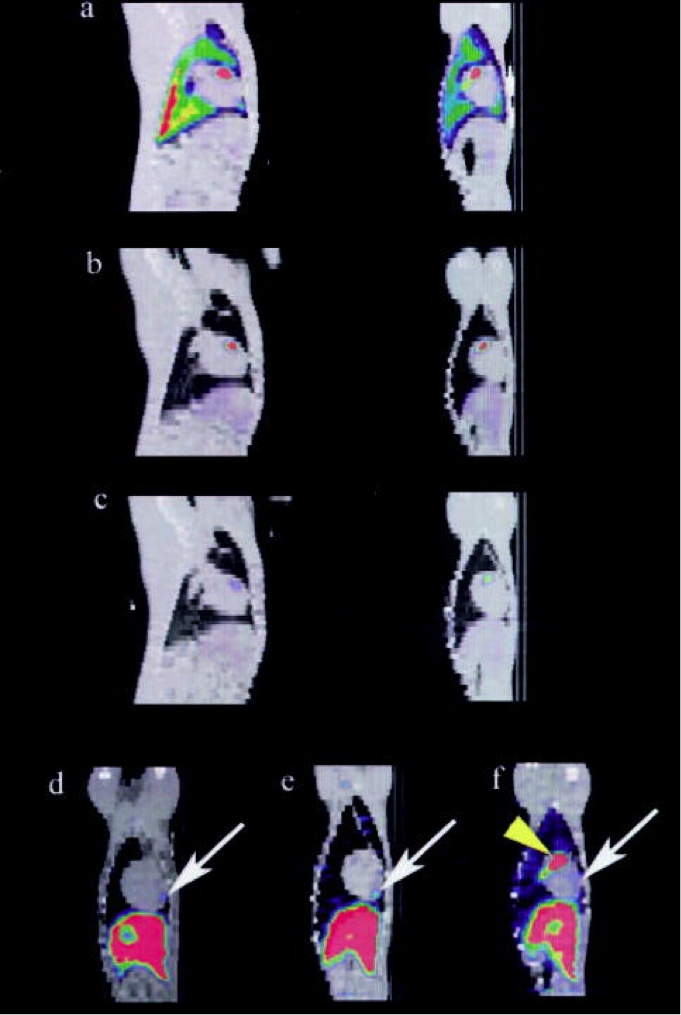

Hình ảnh mặt cắt trước ( bên phải), mặt cắt dọc ( bên trái) của kết quả chụp SPECT/ CT, thể hiện sự hấp thụ ngày 1 ( a), ngày 2 ( b), ngày 7 ( c) tại tâm thất trước của tim động vật. Hình ảnh cuối chụp thời điểm ngày thứ 5 ~ 8, khu vực hấp thụ MSC (mũi tên) thể hiện trên ảnh chụp mặt cắt bên của 3 đại điện.